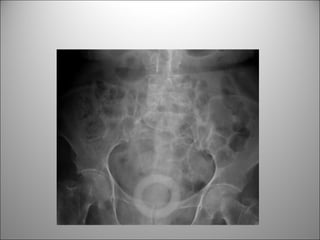

PATOLOGÍA FRECUENTE

LITIASIS

MIOMAS

LITIASIS BILIAR

CALCIFICACIONES AORTICAS